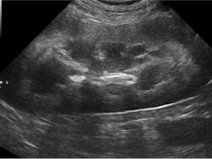

- décrire la présentation clinique des principaux cancers rencontrés dans l’espèce féline et les outils (biologiques, imagerie) indispensables de la démarche diagnostique ;